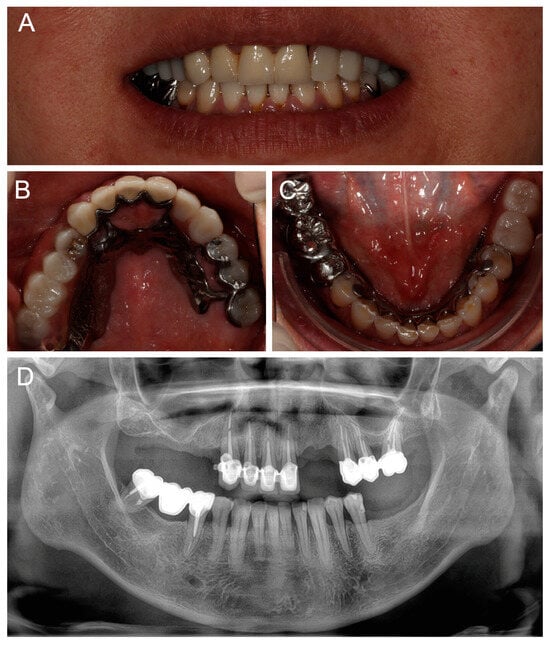

2.1. Initial Consultation

Clinical investigations showed partially edentulous regions of the maxilla (Kennedy class II, #14-17, #22-23, #27) and mandible (Kennedy class II, #36-37). Tooth #13 had a significant vestibular cervical lesion and the maxillary teeth had several composite restorations. Tooth #12 had a mesio-palatal rotation and tooth #44 had a slight extrusion. In the mandible, a satisfactory metal bridge replaced tooth #46. No alteration of the vertical dimension of occlusion (OVD) was observed. The smile line only revealed gingival embrasures (Class III according to Liébart classification). The patient did not wish to correct the misaligned gingival margins of the maxillary central incisors. The panoramic radiograph revealed that all the maxillary residual teeth had been treated endodontically, and teeth #15 and #22 had recently been removed (Figure 1). Tooth #27 was mesially positioned in place of tooth #26 probably due to an uncompensated extraction in the past.

Figure 1. Initial panoramic radiography.